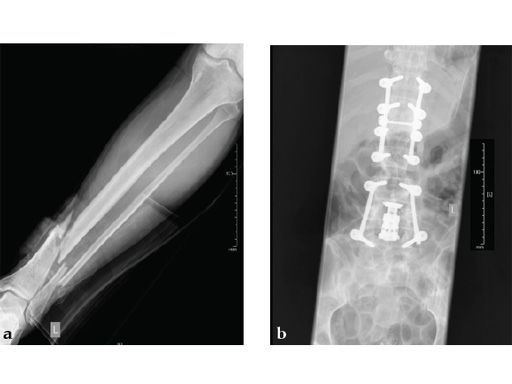

Case 1: A 33-year-old man with a third degree open fracture of his left tibia was initially treated with an external fixator and unilateral compartment release. He had undergone ACL reconstruction in the past.